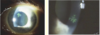

Ocular herpes definition

HSV infection of the conjunctiva w/swollen eyelids

(If the cornea is involved it is herpes simplex keratitis)

Herpes simplex keratitis (aka Dendritic Keratitis) deadens _______ and forms a _____ pattern

- nerves

- Virus branches out in the dendritic pattern

Dendritic keratitis AKA herpes simplex keratitis